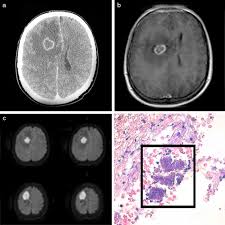

Bienvenidos a este su centro de información sobre la esclerosis múltiple (em). In ms, the immune system—for reasons still not understood—attacks and destroys myelin and the oligodendrocytes that produce it. La esclerosis múltiple es una enfermedad neurológica y degenerativa cuya causa es la desmielinización. Learn more about ms, the types, what causes it, and what signs to. Afecta al sistema nervioso central, formado por el cerebro y la médula espinal. It's a lifelong condition that can sometimes cause serious disability, although it can occasionally be mild. Ivan balicevic boras calle bailarín josé espadero 10/portal 1/3ºa, 03015 alicante tfn.: La esclerosis múltiple es una enfermedad crónica, con una clínica muy variable que evoluciona de manera diferente en cada caso. Calabresi pa, multiple sclerosis and demyelinating conditions of the central nervous system. Multiple sclerosis (ms) is a relatively common acquired chronic relapsing demyelinating disease involving the central nervous system, and is the second most common cause of neurological impairment in young adults, after trauma 19. In multiple sclerosis, the protective coating on nerve fibers (myelin) is damaged and may eventually be destroyed. La esclerosis múltiple (em) o esclerosis de placas es una enfermedad neurológica crónica de naturaleza inflamatoria y autoinmune caracterizada por el desarrollo de lesiones desmielinizantes, y de daño axonal en el sistema nervioso central. Multiple sclerosis (ms), also known as encephalomyelitis disseminata, is a demyelinating disease in which the insulating covers of nerve cells in the brain and spinal cord are damaged.

En la esclerosis múltiple, la histología o estudio de los tejidos del sistema nervioso reveló que hay un proceso de inflamación que daña la capa de mielina pueden compararse tratamientos en función de la histología de la esclerosis múltiple, diseñando planes terapéuticos con aquellos que han. Esclerosis multiple la degeneración axonal es un proceso que ocurre como consecuencia de una amplia variedad de trastornos metabólicos, tóxicos, hereditarios e inflamatorios los impulsos nerviosos que pasan por esos sitios se interrumpen y en ocasiones quedan totalmente bloqueados.(5). Antonio robles gentile médico c.c., centros asistenciales getafe y pinto correspondencia: Multiple sclerosis (ms) causes, signs and general information at patient.info. Este material puede ser reproducido total o parcialmente para fines de diseminación y capacitación.